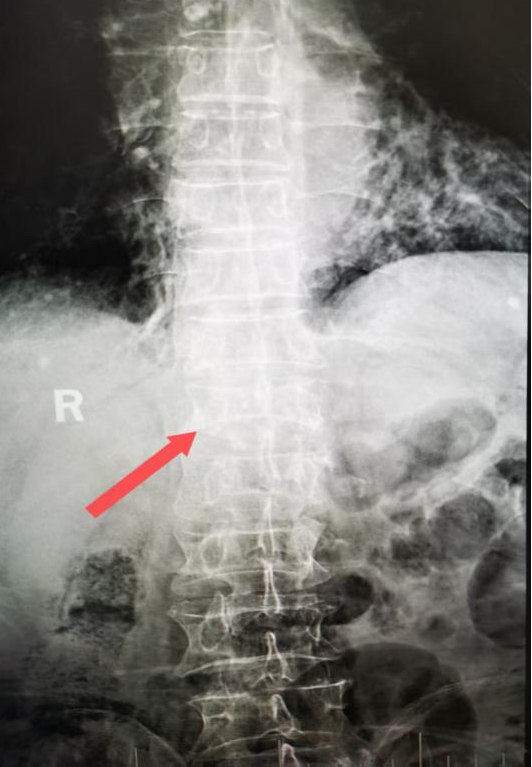

术前CT三维重建显示 第12胸椎压缩骨折(箭头所示)